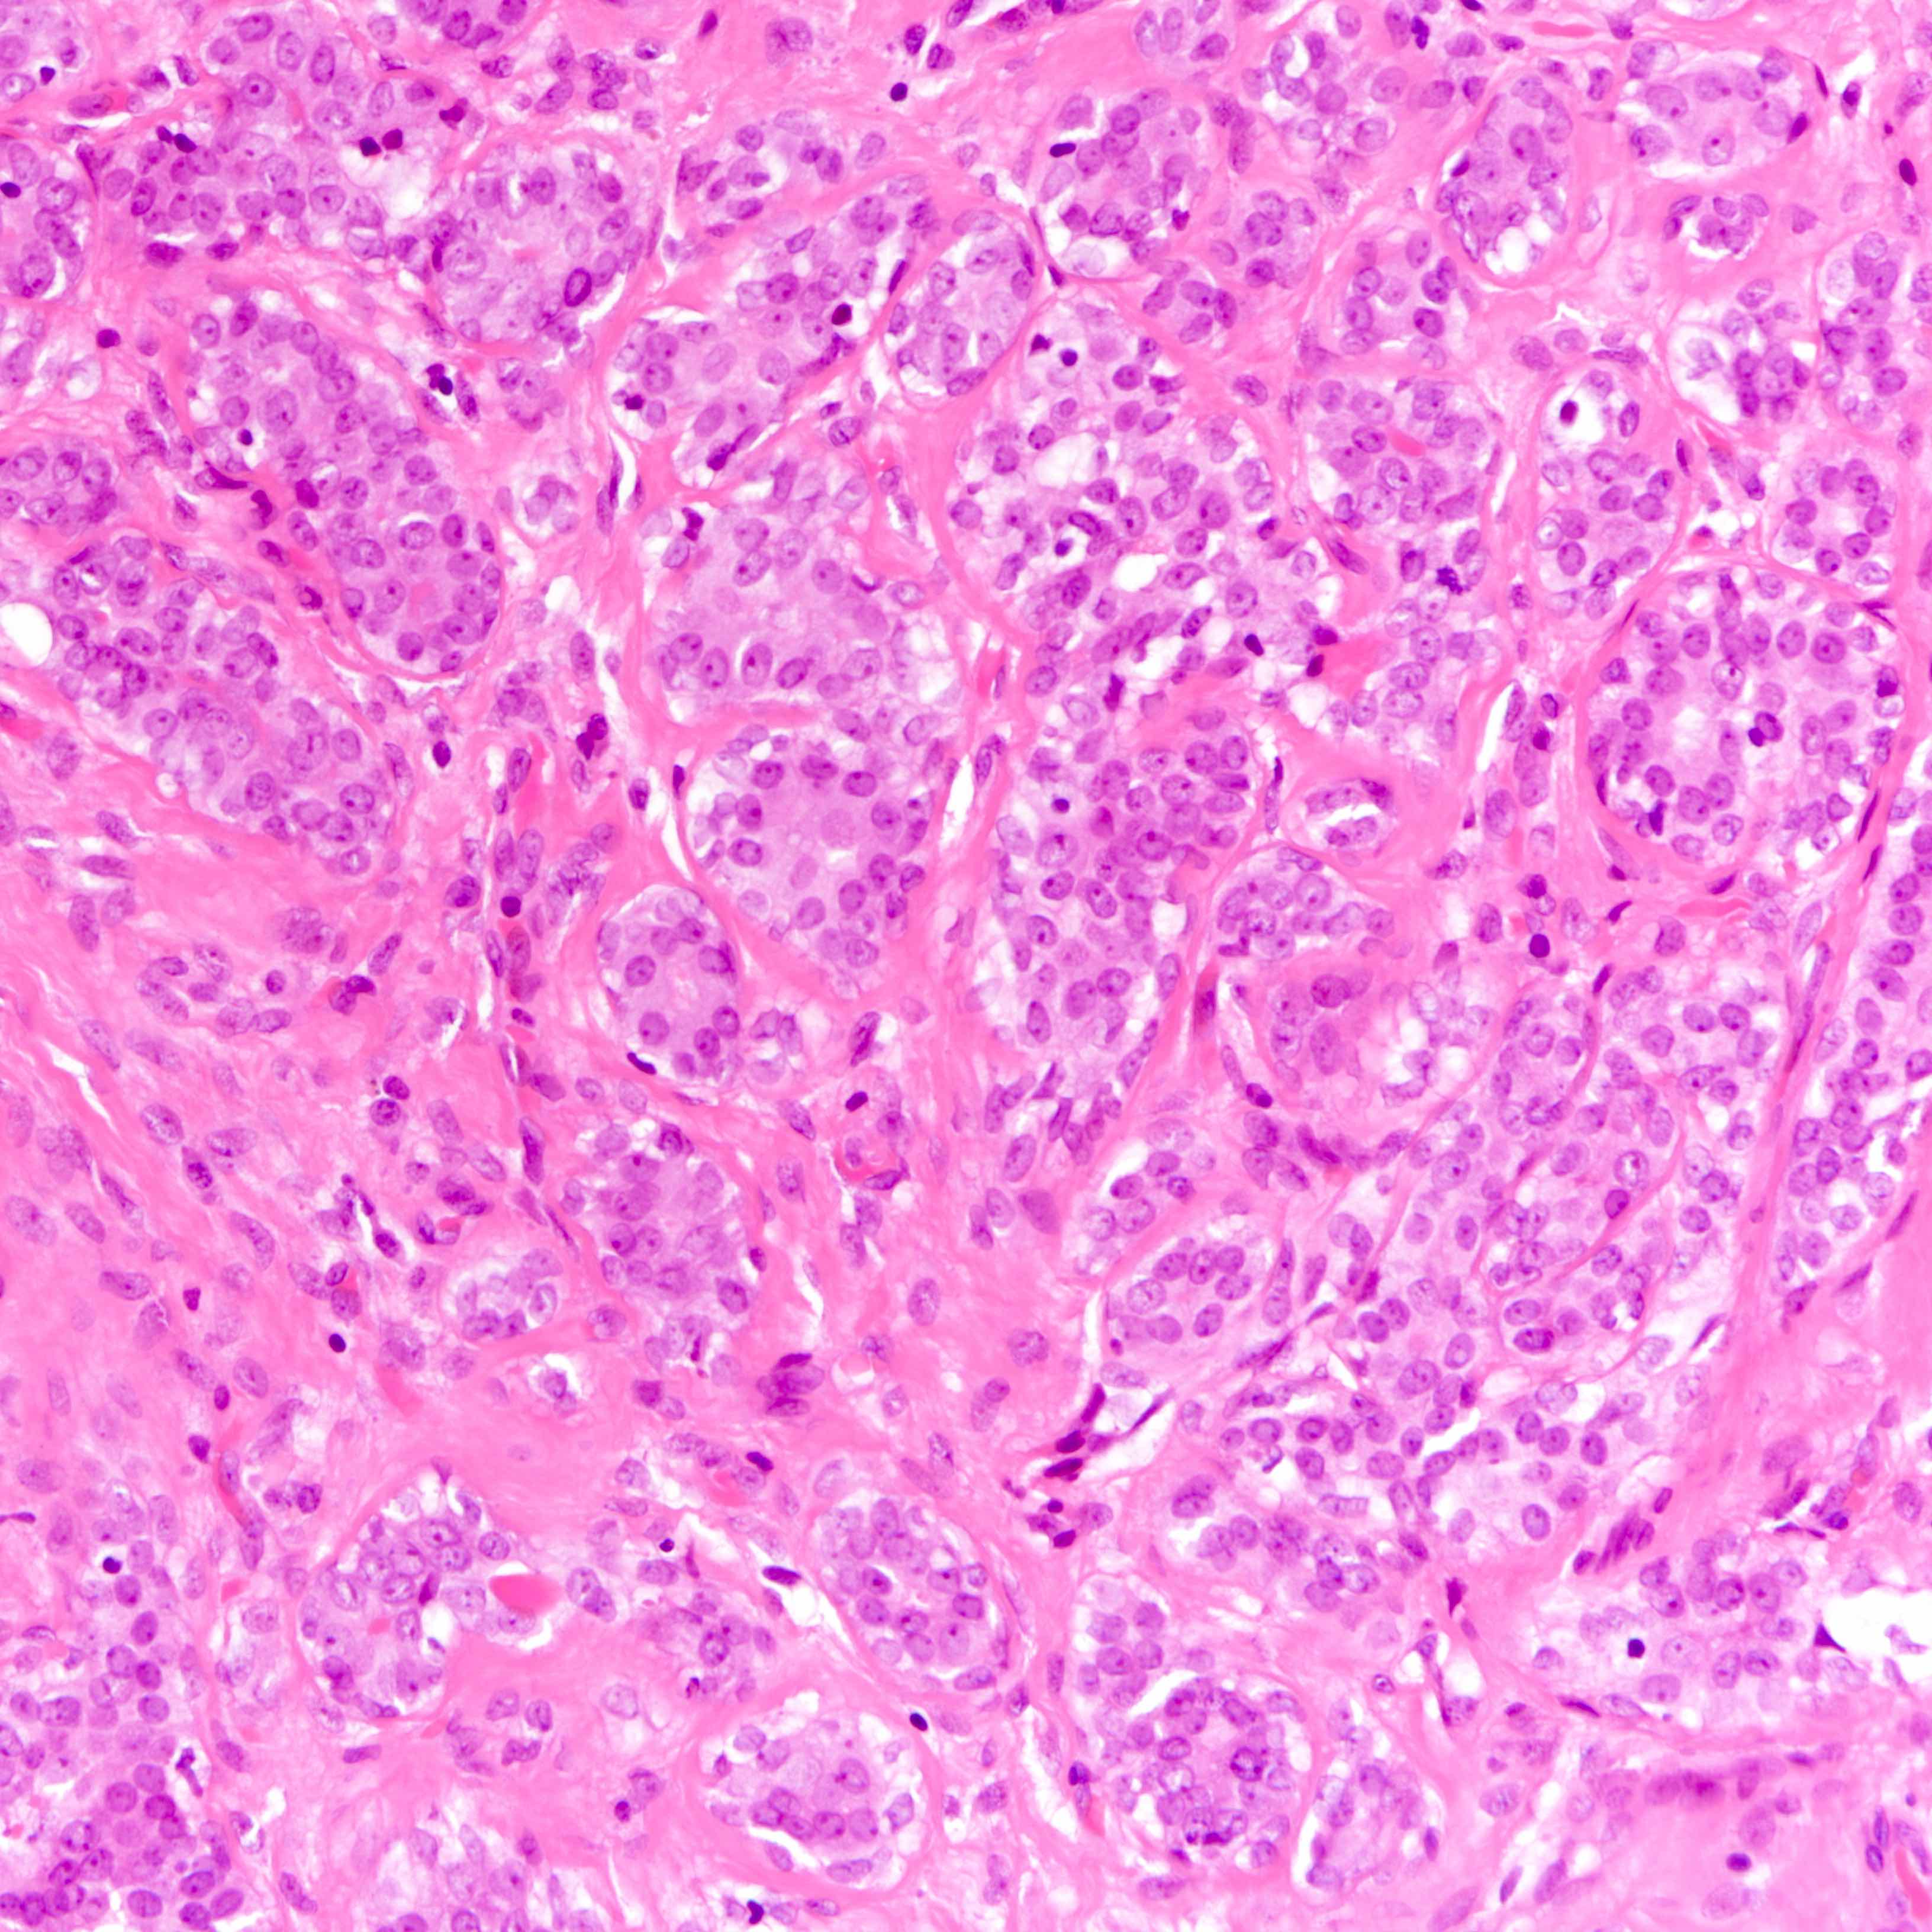

- Well defined borders

- Sparse fibrovascular stroma intervening tubules

- Small, uniform, closely packed round tubules (Clin Med Insights Pathol 2018;11:1179555718757499)

- Lined by an inner layer of luminal epithelial cells and an outer layer of myoepithelial cells

- Rare mild atypia and mitotic figures does not exclude diagnosis

- Lined by an inner layer of luminal epithelial cells and an outer layer of myoepithelial cells

Microscopic (histologic) images

Contributed by Joshua J.X. Li, M.B.Ch.B. and Gary M. Tse, M.B.B.S.

Contributed by Jijgee Munkhdelger, M.D., Ph.D. and Andrey Bychkov, M.D., Ph.D.